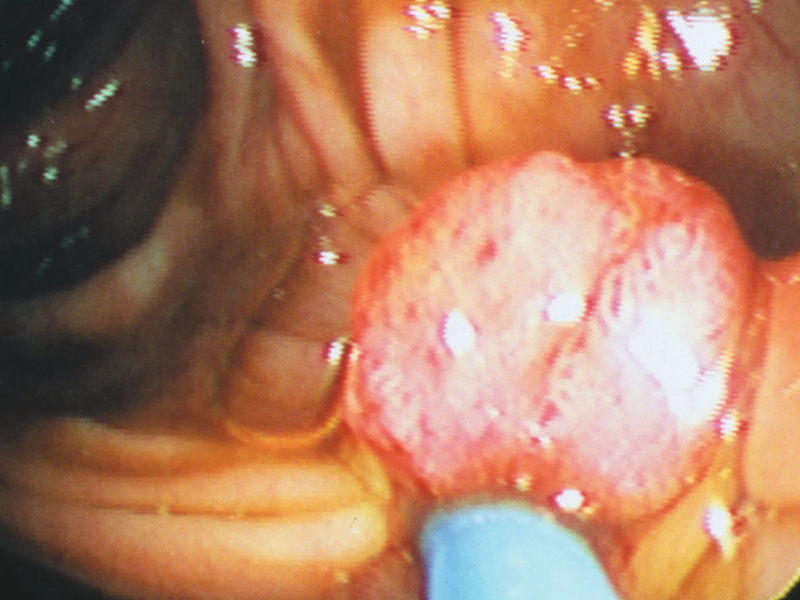

| 2024 年 12 月 6 日,抗癌網紅卜娜娜的社交帳號發布訃告,證實其於當日凌晨在醫院離世,年僅 25 歲。這位堅強與病魔抗爭的年輕女性,生前憑藉樂觀精神鼓舞無數人,卻在確診癌症僅一年半後不幸辭世。 曾是輔警 勇敢面對人生困境 卜娜娜,原名盧文娜,生前是一名輔警。根據其社交媒體介紹,卜娜娜自幼生活艱辛,父母在她初中時離異,她靠打工完成學業,曾從事銷售和擺攤工作,但仍堅守成為警察的夢想,最終成為一名輔警。2023 年 5 月,她被診斷出罹患鼻竇部腺泡狀橫紋肌肉瘤,一種惡性程度極高的罕見癌症。 儘管癌症已屬晚期,卜娜娜仍選擇以積極心態與病魔抗爭。確診後的一年多時間,病情迅速惡化,她經歷了視力幾乎喪失和頭髮脫落,但依然堅守社交媒體平臺,分享她面對生命挑戰的故事,激勵無數網友。 生命的最後一刻:感恩與希望 在 2024 年 11 月 18 日,卜娜娜更新了最後一條動態。她寫道:「雖然是冬天了,但雲南的冬天卻很溫暖,有陽光,有媽媽的愛,有妹妹的陪伴,還有你們,我很知足。」這段溫暖的話語成為她留給外界的最後記憶,也展現出她面對人生困難時的從容與感恩。 什麼是橫紋肌肉瘤? 橫紋肌肉瘤是一種源自橫紋肌細胞或向橫紋肌細胞分化的間葉細胞的惡性腫瘤,在兒童軟組織腫瘤中最為常見,但在成年人中較為罕見。根據不同類型,橫紋肌肉瘤多見於 8 歲以下的兒童或青春期男性,發病率為每十萬人約一例。此類癌症生長迅速,極易短時間內出現轉移,屬於高度惡性腫瘤之一。 在全球範圍內,橫紋肌肉瘤的發病率極低,但在人口基數龐大的中國,每年新增病例數量仍達 4 萬人之多。由於該病起病隱匿且發展迅速,患者的生存挑戰極大,治療過程亦十分艱辛。 卜娜娜的故事觸動人心 卜娜娜的抗癌經歷不僅展現了面對生命苦難的勇氣,更引發公眾對罕見疾病和患者生存狀況的關注。她短暫而璀璨的一生,留下了感動與啟發,也為大眾帶來了更多關於珍惜生命的反思。 |